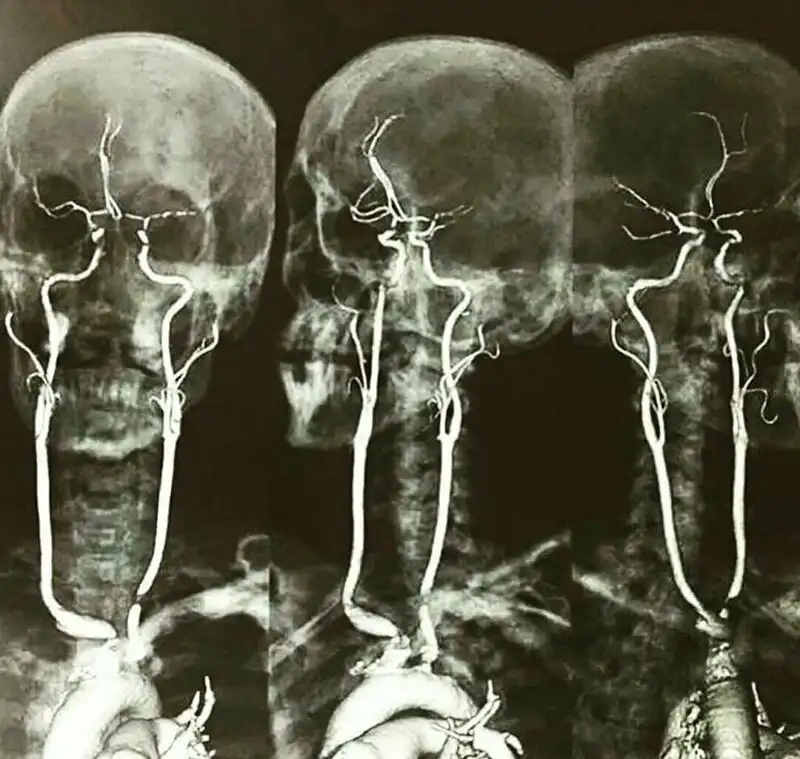

А это рентген с контрастированием сонных артерий. Выглядит жутковато только для непосвященных